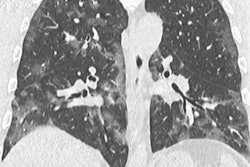

Currently, the playlist offers two videos. The first is a special report about radiology's role in fighting the virus. Nicola Sverzellati, a professor from the University of Parma in Italy, shares his experiences of working with patients and image management in Europe's most affected area. He also discusses the challenges Italian radiology departments face and the diagnostic flowchart his team has developed since the outbreak.